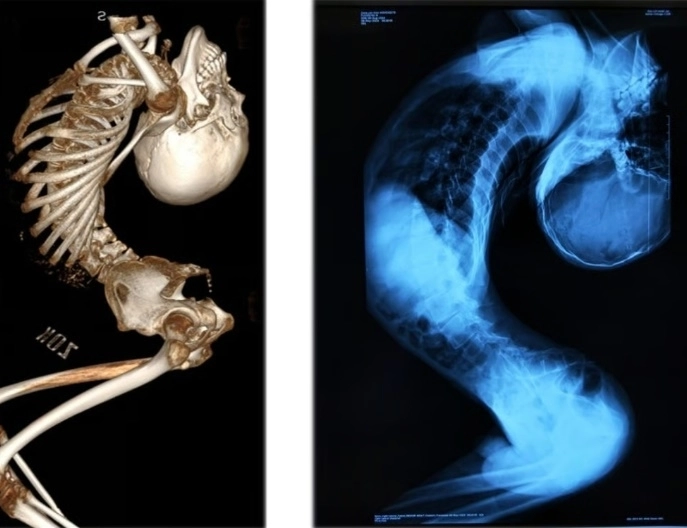

180도로 휘어진 척추로 인해 ‘폴더 소년(접힌 소년)’이라 불린 중국 청년이 대수술 끝에 몸을 곧게 펴는 데 성공했다.

중국 산둥성 출신인 장씨는 척추 관절과 인대에 심각한 염증을 일으키는 희귀 질환인 ‘강직성 척추염’을 앓아 목과 척추가 뒤로 심하게 굽은 채 살아왔다.

이 희귀한 질환으로 인해 그의 몸은 ‘Z자’ 형태로 접혀 머리와 엉덩이 간격은 손바닥 한 뼘에 불과했고, 접힌 키는 80cm에 불과했다.

이후 지난해 8월 그는 청두의 척추 교정 권위자인 량이젠 교수에게 경추·흉추·요추 절골술과 고관절 교정 등 총 4차례의 대수술을 받았다.

지난 6월 받은 마지막 수술은 12시간 넘게 이어졌으며, 그의 척추는 약 170도 교정됐다.